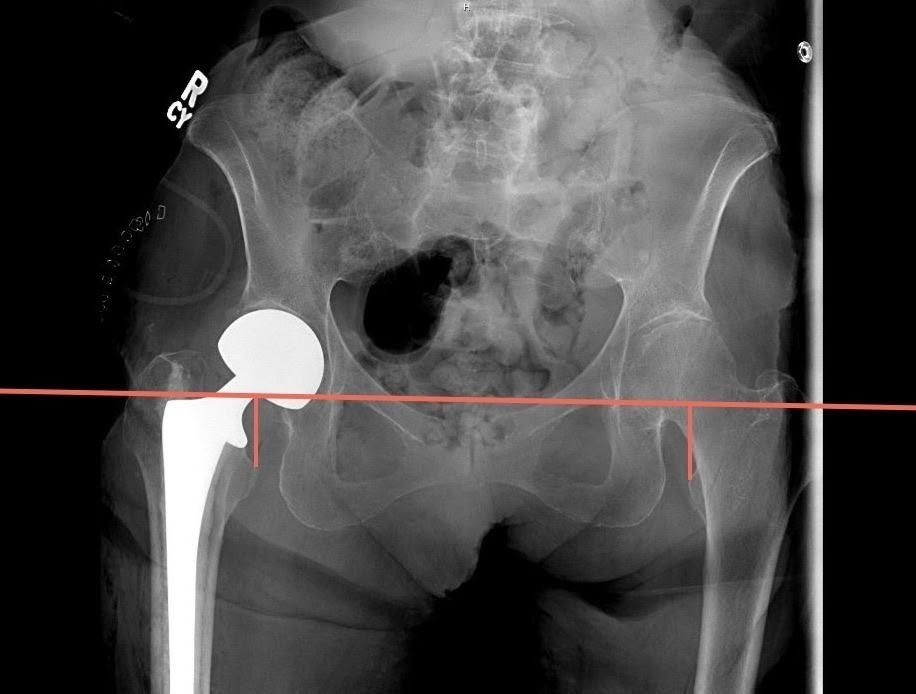

Measurement of LLD was performed using immediate postoperative imaging of an AP pelvis radiograph utilizing the technique described by Ranawat et al.14 This measurement was performed using the difference between a horizontal line drawn from the inferior aspect of the teardrop of the pelvis to a horizontal line drawn from the most prominent aspect of the lesser trochanter. Positive values were given if the length on the operative side is greater than the contralateral side, and negative values were given if the operative side was shorter (Figure 3).